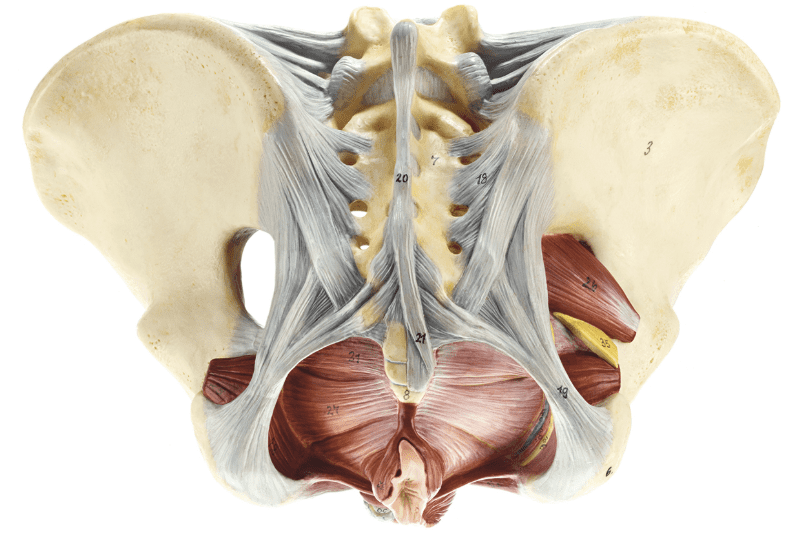

Pelvik Taban

PELVİK TABAN KASLARI VE POSTÜRÜN ÖNEMİ

Pelvik taban kasları, vücudun en alt bölgesinde yer alarak organları destekleyen, idrar ve dışkı kontrolünü sağlayan, aynı zamanda core sistemin bir parçası olan kritik kas gruplarıdır. Postür ise vücudun dik, dengeli ve doğal hizalanmış duruşunu ifade eder. Bu iki unsur arasındaki ilişki, genel sağlık açısından göz ardı edilemeyecek kadar güçlüdür. Doğru postür, pelvik taban kaslarının doğal işlevlerini korumasına yardımcı olurken; yanlış duruş, bu kasların zayıflamasına ve çeşitli sağlık sorunlarına yol açabilir.

PELVİK TABAN VE CORE SİSTEM İLİŞKİSİ

Pelvik taban kasları, core sistemin temel taşlarından biridir. Core kasları; karın, sırt ve pelvik bölgeyi kapsayan, vücudun merkezini stabilize eden kas gruplarıdır. Postür bozuklukları, core sistemin bütünlüğünü zayıflatır ve pelvik taban kaslarının işlevini olumsuz etkiler. Bu nedenle doğru postür, core kaslarının koordineli çalışmasını destekleyerek pelvik sağlığını korur.